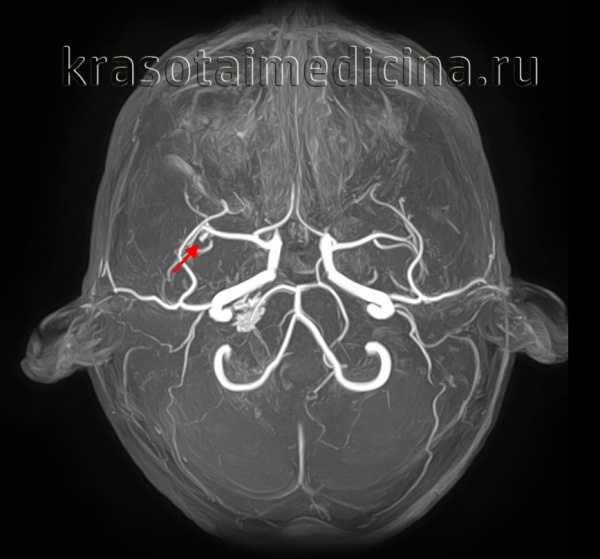

• МР-ангиография:

о 3D TOF: в > 90% случаев чувствительна к аневризмам > 3 мм

о Субстанции с коротким временем Т1, такие как подострое кровоизлияние, могут имитировать кровоток на МР-ангиографии в режиме TOF